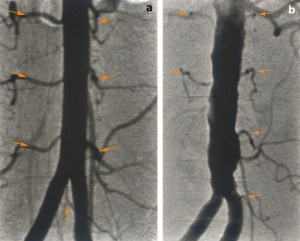

Atherosclerosis can cause disc degeneration, and consequent back problems, by obstructing the blood vessels which feed the lumbar spine.[vii] The autopsy and angiography results below show normal (a), and cholesterol-clogged (b) lumbar arteries and their openings in the wall of the abdominal aorta.[viii]

Figure 2: Aortograph showing (a) pairs of normal 2nd–4th lumbar arteries and (b) occluded and narrowed lumbar arteries.[ix] © 2009 European Society for Vascular Surgery